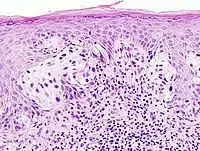

The practice of surgical pathology allows for definitive diagnosis of disease (or lack thereof) in any case where tissue is surgically removed from a patient. This is usually performed by a combination of gross (i.e., macroscopic) and histologic (i.e., microscopic) examination of the tissue, and may involve evaluations of molecular properties of the tissue by immunohistochemistry or other laboratory tests.

A biopsy is a small piece of tissue removed primarily for the purposes of surgical pathology analysis, most often in order to render a definitive diagnosis. Types of biopsies include core biopsies, which are obtained through the use of large-bore needles, sometimes under the guidance of radiological techniques such as ultrasound, CT scan, or magnetic resonance imaging. Core biopsies, which preserve tissue architecture, should not be confused with fine-needle aspiration specimens, which are analyzed using cytopathology techniques. Incisional biopsies are obtained through diagnostic surgical procedures that remove part of a suspicious lesion, whereas excisional biopsies remove the entire lesion and are similar to therapeutic surgical resections. Excisional biopsies of skin lesions and gastrointestinal polyps are very common. The pathologist's interpretation of a biopsy is critical to establishing the diagnosis of a benign or malignant tumor, and can differentiate between different types and grades of cancer, as well as determining the activity of specific molecular pathways in the tumor. This information is important for estimating the patient's prognosis and for choosing the best treatment to administer. Biopsies are also used to diagnose diseases other than cancer, including inflammatory, infectious, or idiopathic diseases of the skin and gastrointestinal tract, to name only a few.